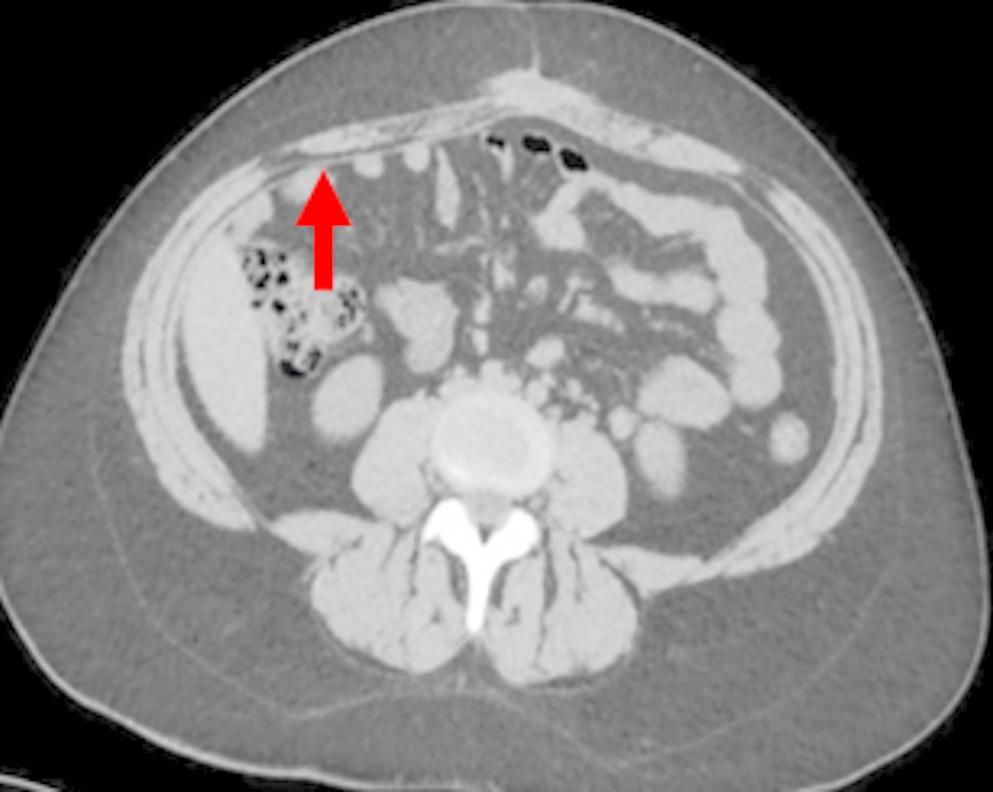

All participating radiologists were subspecialty-trained in body CT with extensive experience in postoperative CT interpretation, including a minimum of five VHR-related studies weekly. Each radiologist independently assessed 18 CT scans performed two years post-VHR. The 2- year post-operative timepoint was selected based on several considerations: (1) complete mesh incorporation and tissue remodeling typically occurs by 12–24 months, providing stable imaging characteristics; (2) this timeframe represents when many patients present with recurrent hernias requiring reoperation; and (3) it minimizes acute post-operative changes that could confound mesh visualization while maintaining clinical relevance for surgical planning. Radiologists completed a structured questionnaire to specify mesh location and type. The VHR planes were classified according to the European Hernia Society’s International Classification of Abdominal Wall Planes (ICAP) (Parker SG, et al. International classification of abdominal wall planes (ICAP) to describe mesh insertion for ventral hernia repair. Br J Surg. 2020;107(3):209–217). The planes assessed included: (1) retrorectus plane - mesh positioned posterior to the rectus muscle and anterior to the posterior rectus sheath; (2) retromuscular plane - accessed only after transversus abdominis release (TAR), with mesh extending laterally beyond the semilunar line; (3) preperitoneal plane - mesh positioned between the peritoneum and transversalis fascia; and (4) intraperitoneal plane - mesh placed within the peritoneal cavity (Fig. 1). All meshes used in this study were permanent synthetic polypropylene and categorized by density. Heavy-weight synthetic mesh (HWSM) was defined as PROLENE® Mesh, manufactured by Ethicon with a density of 95 g/m² (Fig. 2). Medium-weight synthetic mesh (MWSM) referred to Bard™ Soft Mesh, with a density of 43 g/m², and light-weight synthetic mesh (LWSM) corresponded to Ultrapro™ advanced, with a weight of 26 g/m² (Figs. 3 and 4) Detailed characteristics for all 18 cases, including mesh specifications and CT parameters, are provided in Supplementary Table 1. Additionally, the study incorporated CT scans from two control groups: a negative control group with patients who had never undergone abdominal surgery, and a positive control group with patients who had undergone laparotomy without VHR. Control CT scans were obtained at variable timepoints: positive control scans (laparotomy without VHR) were acquired 3–6 months postoperatively to capture healed surgical changes without mesh, while negative control scans (no prior abdominal surgery) had no timing restrictions as they served to demonstrate normal abdominal wall anatomy. The 3–6 month timepoint for positive controls was selected to ensure complete laparotomy healing while avoiding long-term tissue remodeling that might obscure surgical plane distinction. While this creates temporal mismatch with 24-month VHR scans, the primary diagnostic task focuses on mesh presence/absence rather than temporal evolution of surgical changes. This timepoint captures healed surgical changes without mesh-related artifacts, providing appropriate control for radiologist assessment. All radiologists were informed of the inclusion of these control scans in the study.

Fig. 4

Light Weight Mesh

Bild vergrößern